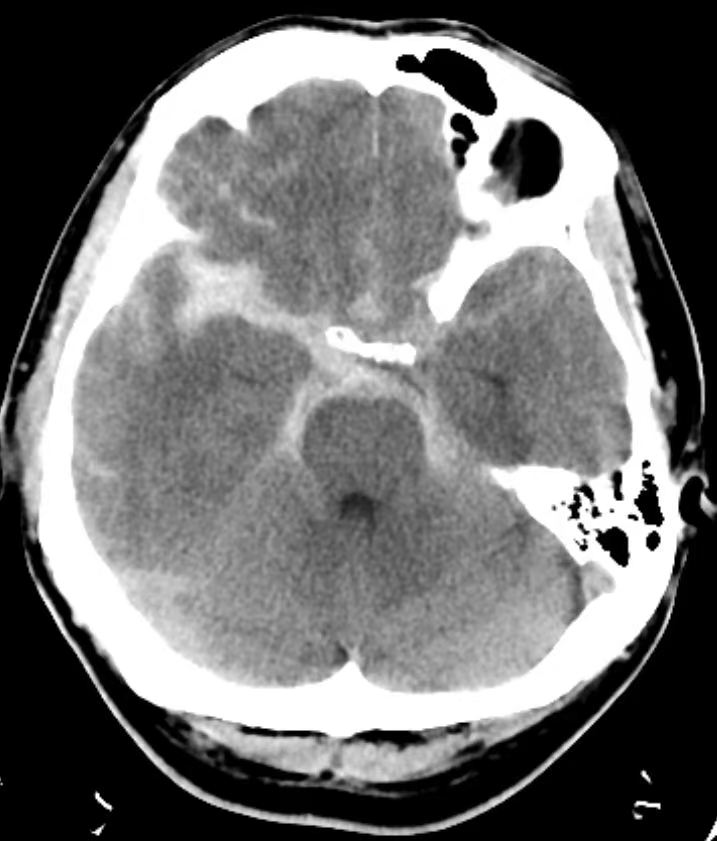

患者男性,40岁,既往体健。主因“头痛2天,加重1天”就诊于清华大学附属垂杨柳医院急诊科。查体:嗜睡,可对答,双侧瞳孔等大。急诊头颅CT显示蛛网膜下腔出血,CTA提示右侧大脑中动脉M1段分叉动脉瘤。

CT提示蛛网膜下腔出血